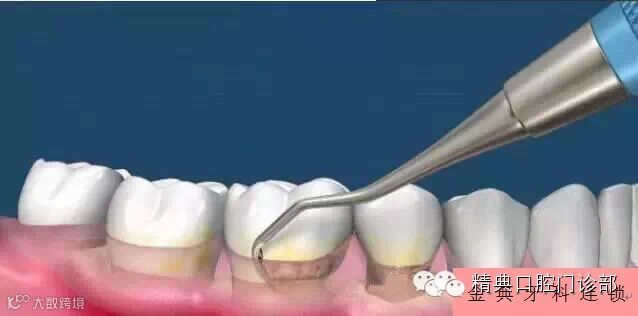

图片十、医生或洁牙师首先会用超声波将牙面上比较坚硬的牙结石清除掉。

图片十一、超声波是靠震动来铲除牙面上坚硬的牙结石,而不是靠打磨来清除的,所以您不用担心洗牙会将牙齿洗薄。

图片十二、超声波洁牙头表面是光滑圆顿的,所以不会对牙齿产生打磨的效果,同样清除下来的牙结石也是一整块一整块的,如果是打磨的话,清除下来的牙结石应该是成粉末状,这一点也可以证明洗牙不会将牙齿磨薄。